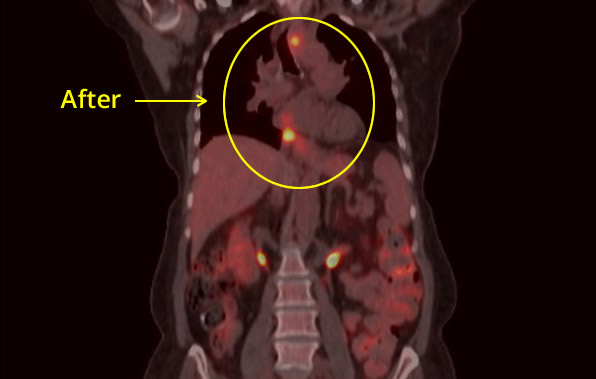

Esophageal CXR After